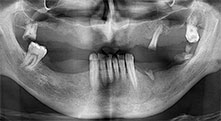

Bratu: Preferimos realizar las osteotomías en la línea oblicua externa de la cara posterior del maxilar inferior, y no en la región situada entre los orificios. Tras realizar una incisión en los tejidos blandos, utilizamos las nuevas sierras para definir el contorno de la osteotomía. De este modo, conseguimos una preparación completa en prácticamente el 80 por ciento de los casos. Por otro lado, en algunas ocasiones también utilizamos otros insertos piezoquirúrgicos, así como un cincel para mover el injerto. Para nosotros, esta es una técnica de intervención muy eficaz.